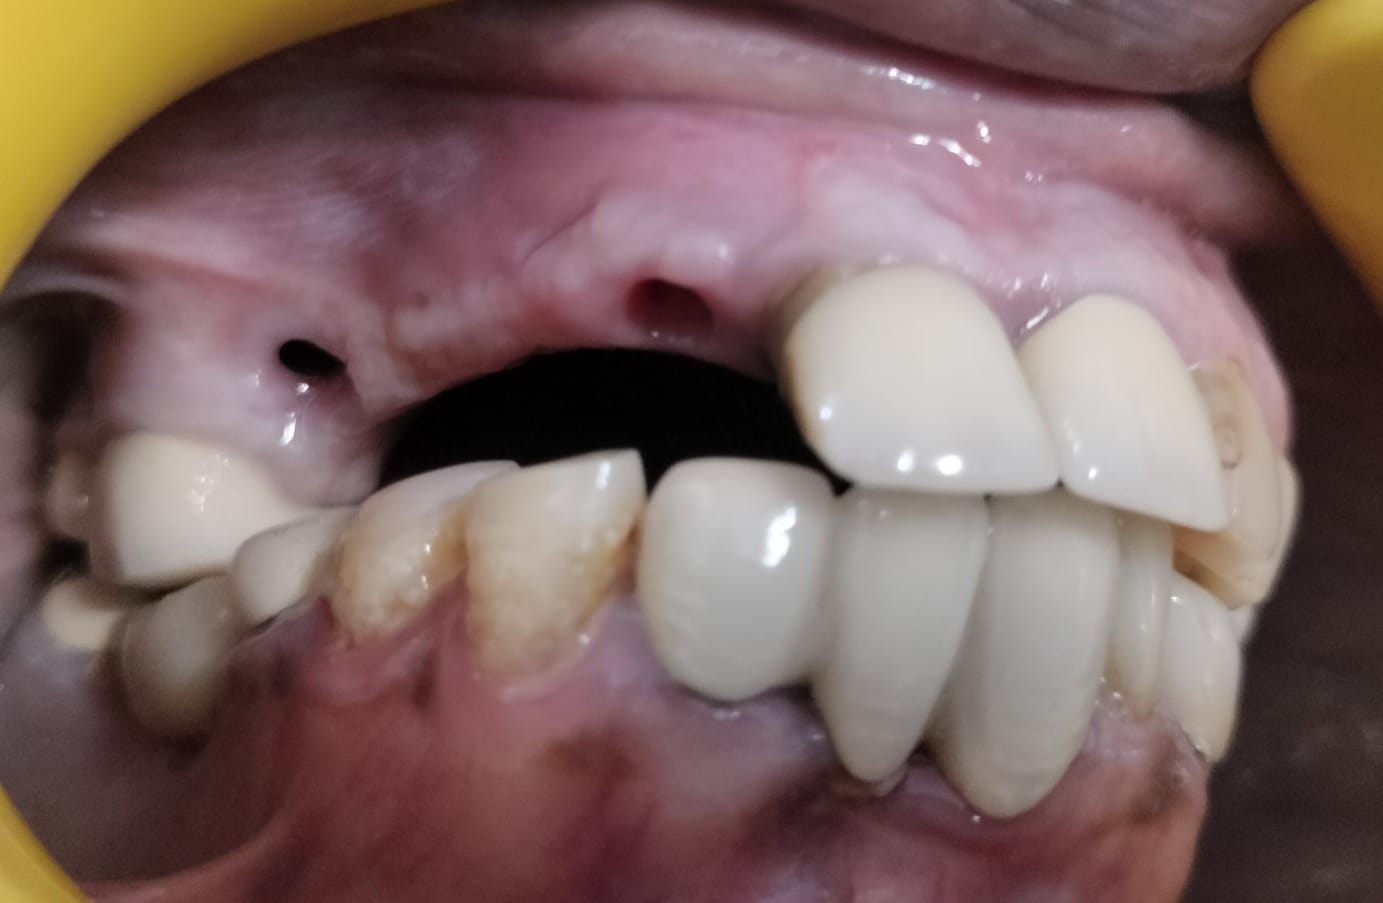

Painless Immediate Implant Treatment

One of the most advanced procedures offered at Dental Lifecare in Sector 71, Noida is the Painless immediate implant technique. Traditionally, patients had to wait several months after tooth extraction before receiving an implant. However, modern technology allows implants to be placed immediately after removing the damaged tooth. This procedure is known as immediate implant after extraction of tooth.

Benefits of immediate implants include:

- Reduced treatment time

- Fewer surgical procedures

- Preservation of jawbone structure

- Faster restoration of smile

- Improved patient comfort

The Painless immediate implant technique is performed using minimally invasive procedures and modern anesthesia techniques, making the treatment comfortable and stress-free for patients.